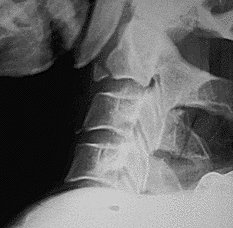

Return to Extension Teardrop Fracture